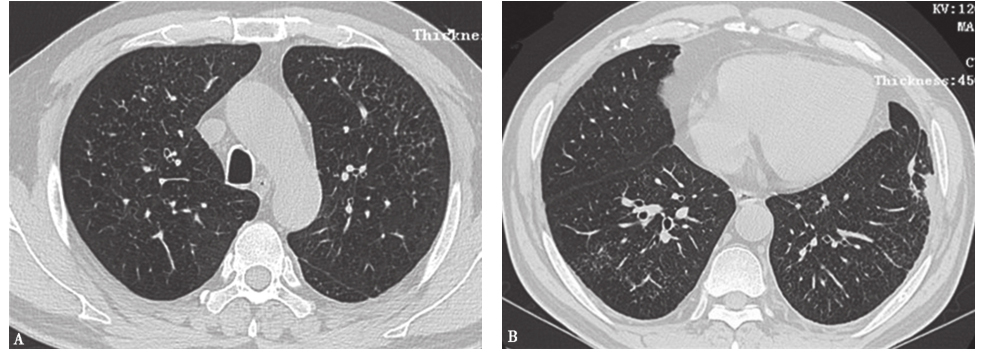

外院胸部CT示两肺散在磨玻璃影、弥漫性小结节影(图1),局部可见牵拉性支气管扩张。

图1外院胸部CT表现

两肺散在磨玻璃影及小结节影(图13),局部网状影,较入院前(图1)明显吸收、好转。